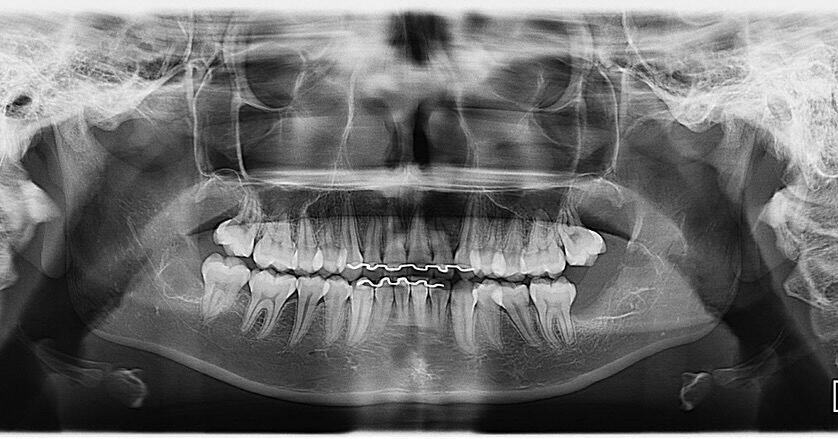

A Patologia Oral e Maxilofacial é a especialidade responsável pelo diagnóstico e tratamento de doenças que afetam a boca, mandíbula e estruturas faciais. Atua na identificação de lesões, cistos e tumores, garantindo diagnóstico preciso e tratamento adequado para preservar a saúde bucal e geral do paciente.